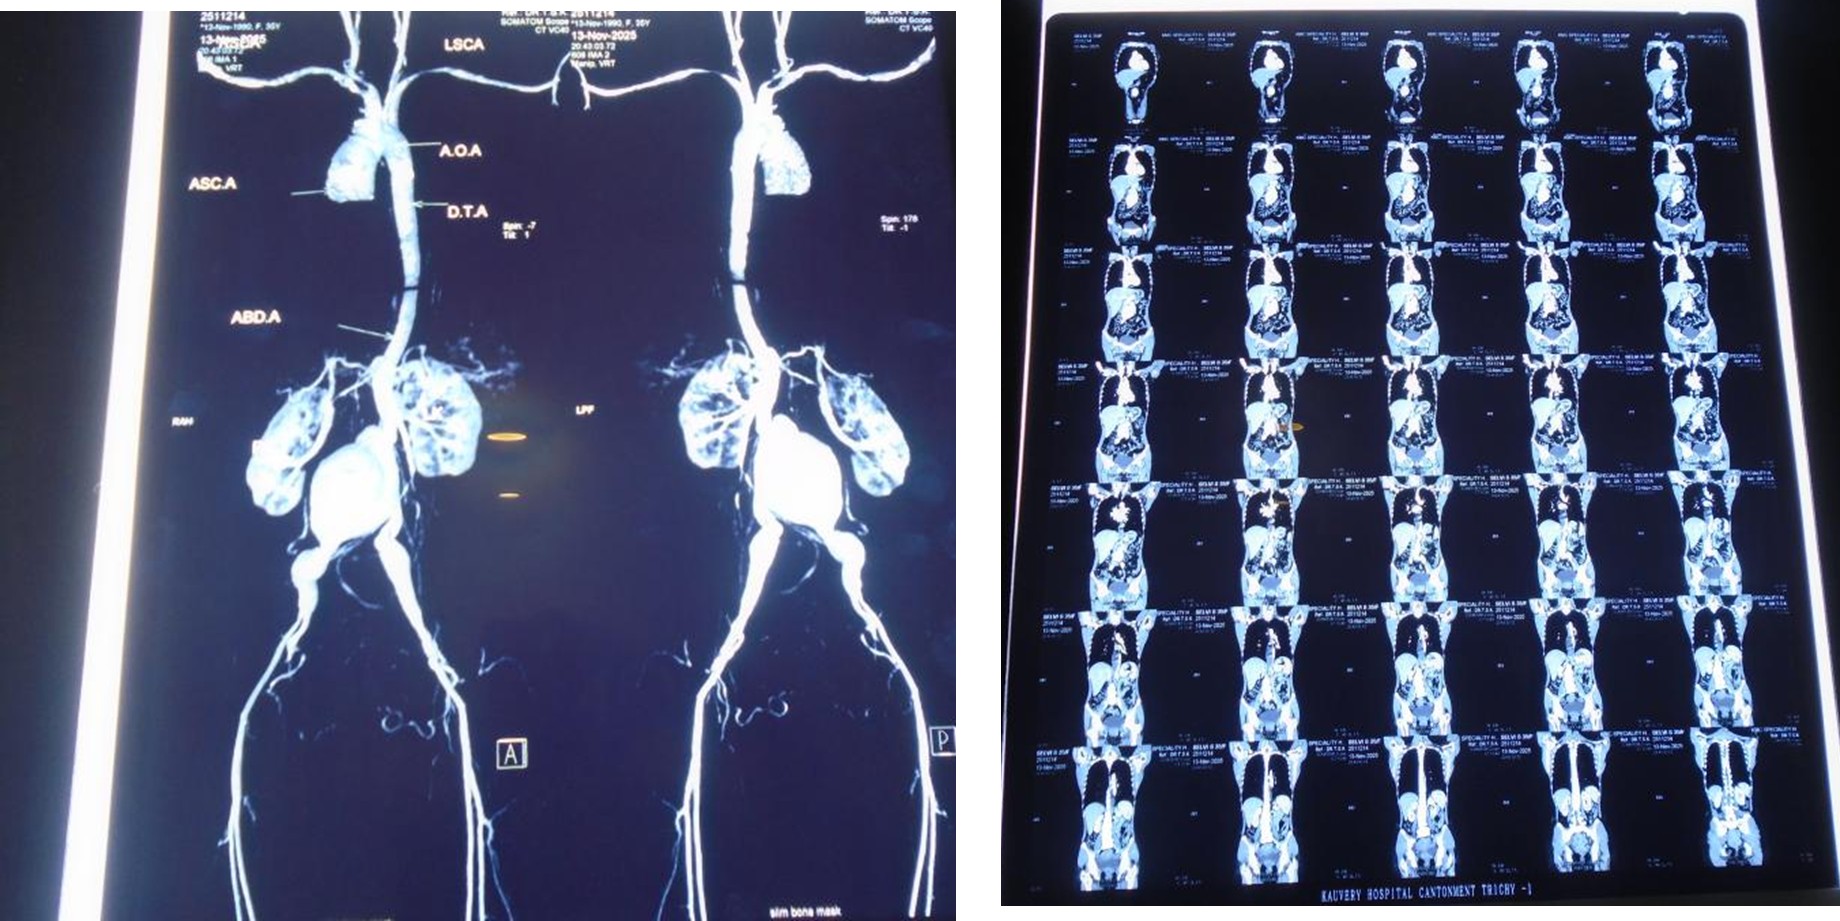

CT Angio

A 39 years old Female, known case of hypothyroidism for 10 years, complaints of sudden onset of pain abdomen since 04/11/2025and was evaluated further management in outside hospital, during her admission patient had episode of vomiting and increased abdominal pain for which CT Angio have been done which showed descending thoracic aorta and abdominal aortic aneurysmal dilation with dissection with aneurysm extending into right CIA. Patient was sent home for conservative management where she developed vomiting again and went to Meenakshi hospital where initial treatment has been given and referred here for further management. On receiving, patient was conscious, oriented and her vitals were stable. CT abdomen done showed DTA aneurysm with dissection infrarenal aortic aneurysm extending up to CIA? Mycotic origin. The patient admitted and planned for staged repair of TAAA. Cardiologist opinion was obtained and his orders were carried out. patient underwent Excision of infra-renal abdominal aneurysm with Aorta Bi-Iliac bypass using 18 × 9 mm unigraft.